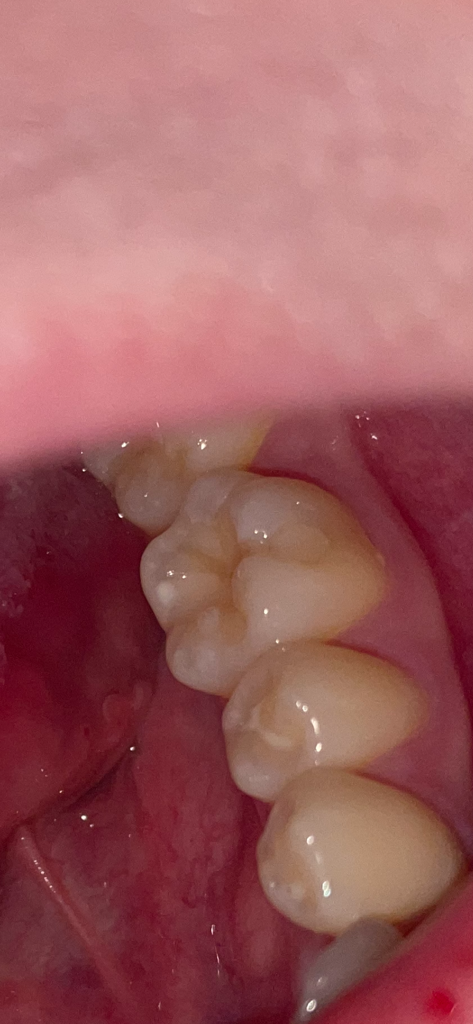

어금니 표면에 구멍이 있는데 심각한간가여ㅠㅠ

여기 표시한 어금니인데요..아마 충치가 있을거같아요..다음주 목요일날정도에 치과에 가려고하는데요ㅠㅠ 그때까지 괜찮겠죠?? 이 충치 많이 깊어보이나요..치료할때 안아팠으면 좋겠어요ㅠ🥺

사진 상으로는 충치가 있어 보이나 깊이 등을 판단하기 위해서는 임상 사진만으로는 힘듭니다. 충치는 겉으로 보기에는 얼마 없어 보여도 삼각형 형태로 충치가 밑으로 확산되기 때문에 더 심할 수 있습니다. 치과 방문 후 방사선 사진 등을 통해 판단해볼 필요가 있습니다. 충치는 단기간에 크게 진행되지 않으니 목요일 날 치과 방문 후 치료하시길 바랍니다.

많이 심해보이지는 않지만 간혹 보기보다 충치가 더 많이 진행된 경우도 종종 있습니다.

충치는 있으실꺼 같긴합니다. 하지만 저기 구멍뚤린건 원래 치아 모양이 그렇게 생긴거에요. 충치 깊이는 엑스레이 사진등을 찍어보시고 판단해야되니 치과에 가셔서 검진을 받아보세요.